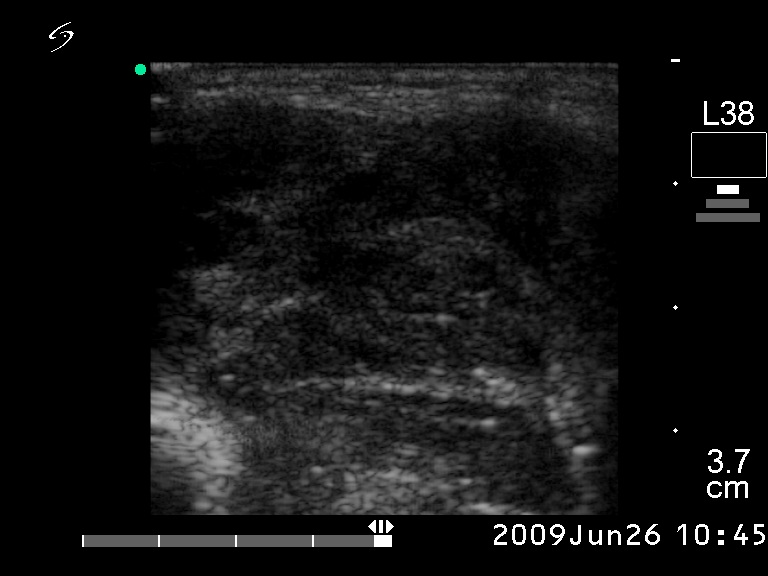

Ultrasonography. The right lobe was hypoechogenic and was not enlarged. The pattern in this lobe corresponded to Hashimoto's thyroiditis. There was a huge tumor in the left thyroid. The pattern of the left lobe varied from moderate to severe hypoechogenicity. The tumor was avascular.